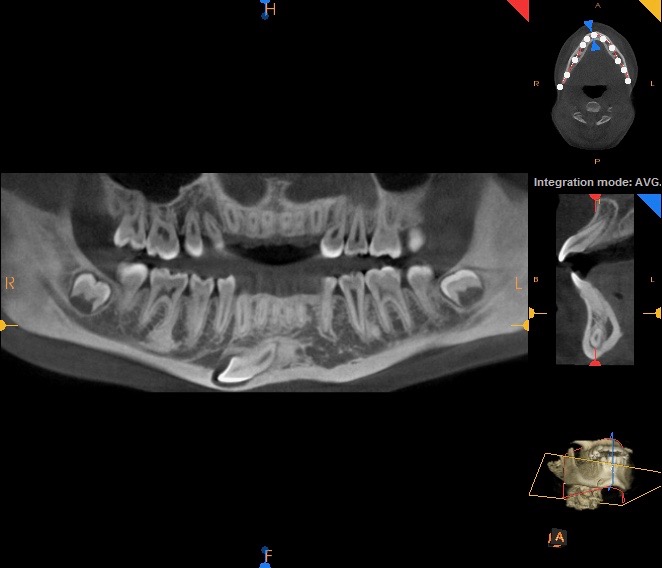

Atraumatic Tooth Extraction and 3-Layer Site Bone Graft For Minor Sinus Perforation

In this video, Dr. H. Ryan Kazemi demonstrates the technique for atraumatic extraction of an upper molar with close proximity to the maxillary sinus. A small sinus perforation was expected and treated by a 3-layer site bone graft approach.